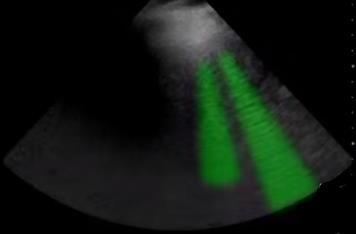

Bild: Lunge, markierte B- und Z-Linie

Markierter Bereich: B- und Z-Linie